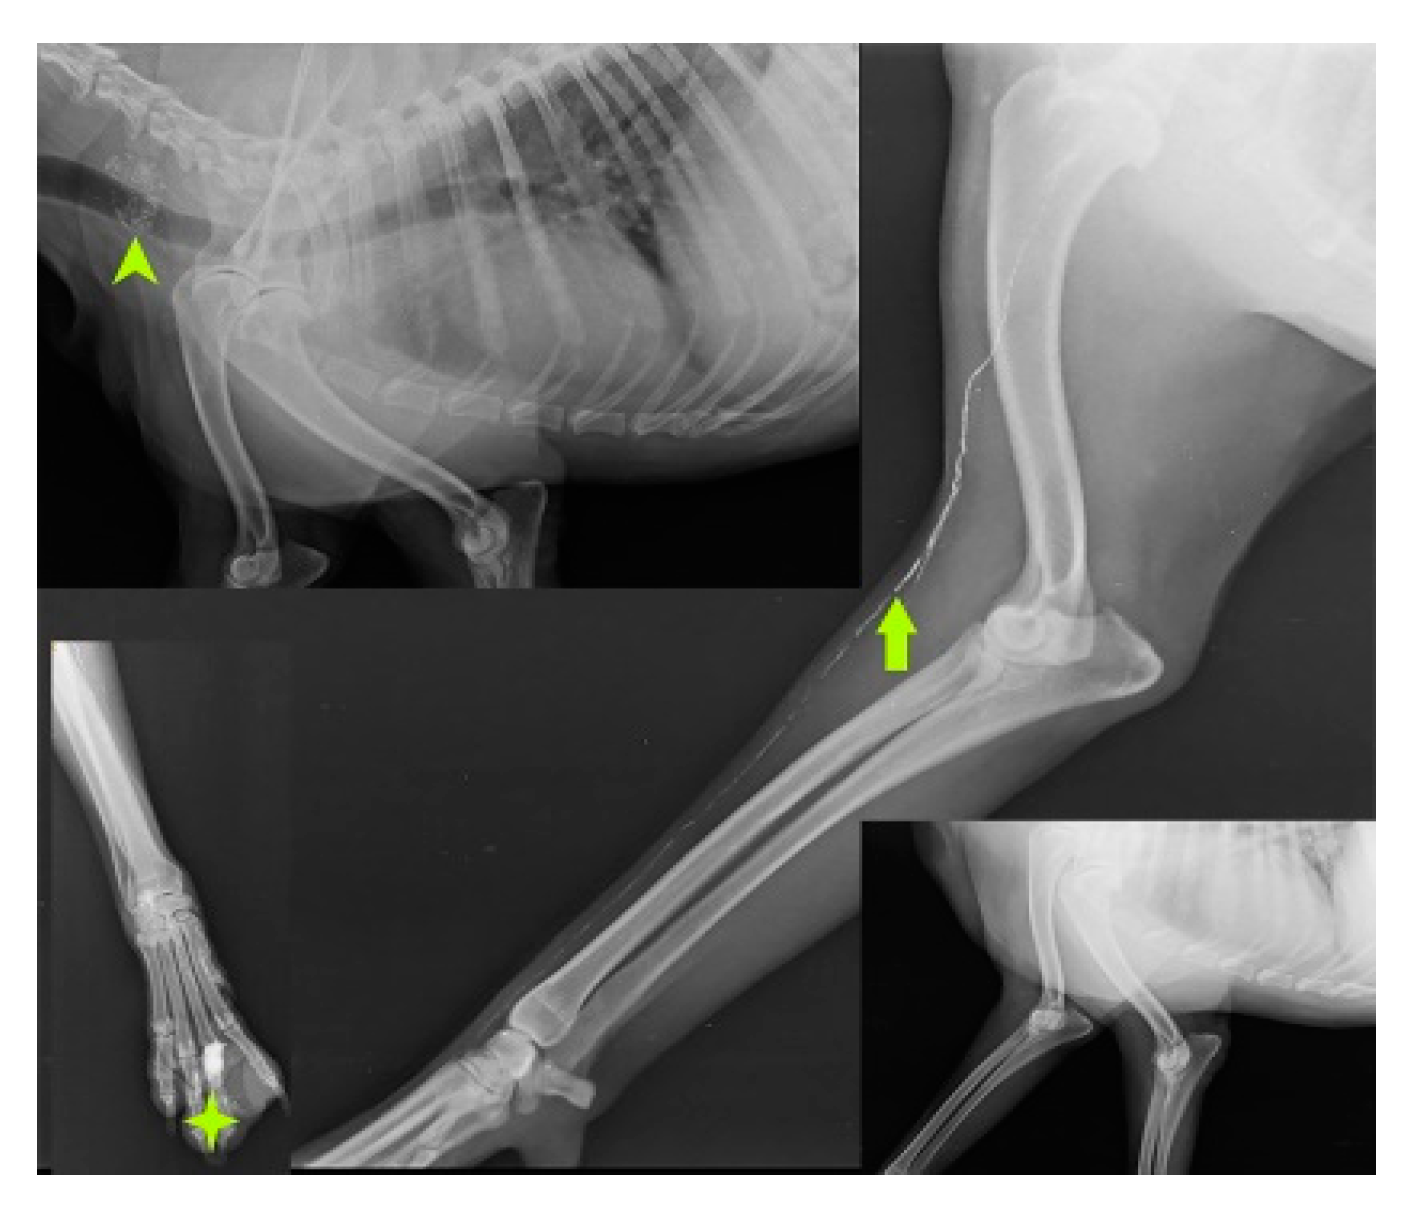

SLN mapping for 20 primary tumors (MCT-11, SCC-3, basal cell carcinoma-1, canine papillomatosis-3, cutaneous plasmocytoma-1, sebaceous gland adenocarcinoma-1) of skin and subcutaneous tissue is performed with four IL methods. MCT weighing 7.8 kg, 3kg, 1.9kg, 1.8kg, 300g, 250g, and lymph nodes weighing 3g, 5g, 10g, up to 90g are excised through en bloc surgical resection with a broad margin. According to the Patnaik grading system (Patnaik et al., 1984), the clinical staging of 11 MCT is Grade III (n=5), Grade II (n=3), and Grade I (n=3). In MCT(n=11), IL with Lipiodol results in 100% detection rate. SLN are detected within 24hr of injections along with gentle messaging in Lipiodol whereas 2 min of injection in iohexol(n=2). Six of the 15 SLN, discovered through cytology and biopsy are determined to be non-metastatic, whereas the other 9 are found to be positive for metastasis. IL was unable to detect any lymph node in rest 5 cases. The SLN for tumors in the front leg is the cervical lymph node as shown in Fig.3.

Figure 3. Cervical lymph node (arrow head) as sentinel lymph node for mast cell tumor (solid star) of front leg.

Preprints 77141 g003

IL with MB employed in the second digit of the right front leg with recurrent MCT perioperatively and cervical lymph node stained blue within 10-15 min of injection as shown in Fig. 4.

Figure 4. cervical LN (inset mass) as SLN detected using MB dye in front leg.

Preprints 77141 g004